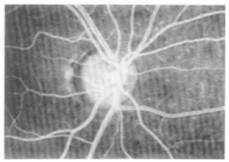

The application of RTD analysis in bio medical engineering is being used at an increasing rate. For example Professor Bob Langer's1 group at MIT used RTD analysis for a novel Taylor-Couette flow device for blood detoxification while Lee et al2 used an RTD analysis to study arterial blood flow in the eye. In this later study sodium fluorescence was injected into the anti-cubical vein. The cumulative distribution function F(t) is shown schematically in Figure 13.5.N-1. Figure 13.5N-2 shows laser ophthalmoscope image after injection of the sodium fluorescence. The mean residence time can be calculated for each artery to estimate the mean circulation time (ca. 2.85 seconds). Changes in the retinal blood flow may provide important decision making information for sickle cell disease and retinitis pigmentosa.

Figure 13.5.N-2 Image of eye after tracer injection. Courtesy of Med. Eng. Phys.2